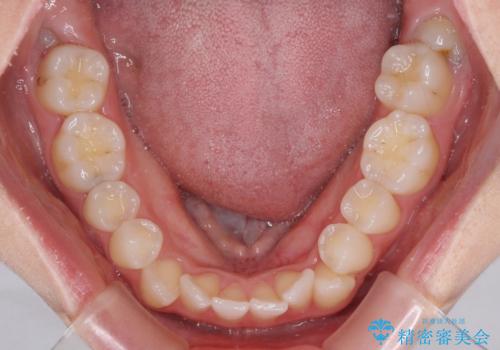

- 上下前歯のデコボコを気にして来院された患者様です。

上顎骨の横幅が狭く、奥歯は上顎よりも下顎が外側にある咬合状態でした。

歯列矯正では基本的に骨格を改善することはできませんが、急速拡大装置(MARPE)を使用することで上顎骨を側方に拡大させることができ、咬合状態を大きく改善することができます。

事前に急速拡大装置で側方拡大を行い、上下を目立たないワイヤー装置により歯列を整えていくこととしました。